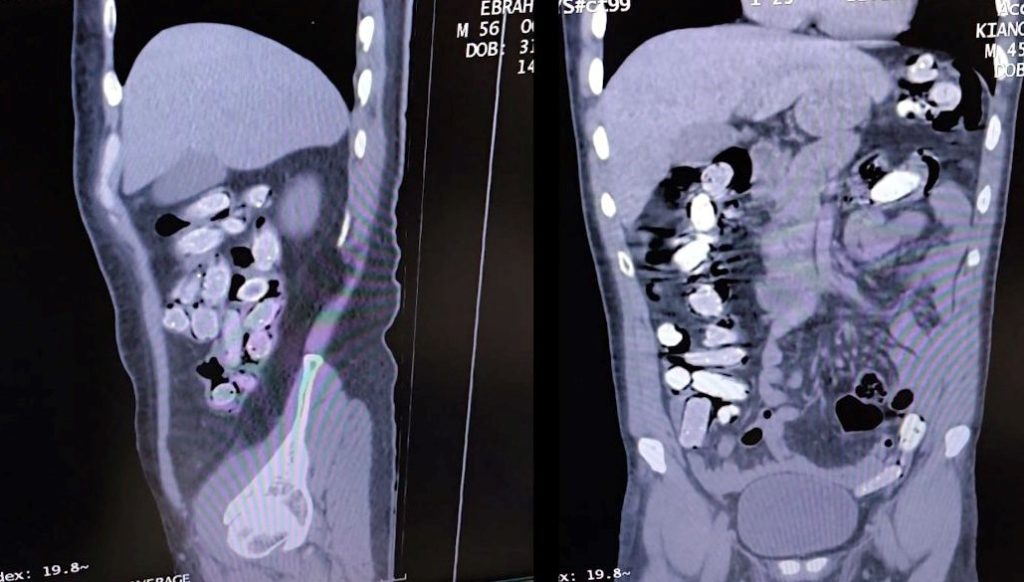

Durumundan şüphelenilen yabancı asıllı iki kuşkulu, gözaltına alındı. Tatvan Devlet Hastanesi’ne götürülen ikişüphelinin röntgen ve tomografi imgelerinde, mide ile bağırsaklarında çok sayıda yabancı cisim olduğu tespit edildi.

Tıbbi müdahale ile iki şüphelinin midesinden paketlenerek yutulan 96 kapsül içerisinde 1 kilo 340 gram afyon sakızı çıktı.